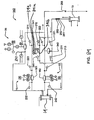

- the system includes four fluid paths: blood; inner dialysate; outer dialysate and dialysate mixing. In some embodiments, these four paths are combined in a single cassette. In other embodiments, these four paths are each in a respective cassette. In still other embodiments, two or more fluid paths are included on one cassette.

- a hemodialysis system having at least two fluid paths integrated into: 1) a blood flow pump cassette, 2) an inner dialysate cassette; 3) an outer dialysate cassette; and 4) a mixing cassette.

- the cassettes may be fluidly connected one to another. In some embodiments, one or more aspects of these cassettes can be combined into a single cassette.

- the hemodialysis system includes a blood flow path, a first cassette defining an inner dialysate fluid path, a dialyzer in fluid communication with the blood flow path and the inner dialysate fluid path, a second cassette defining an outer dialysate fluid path, and a filter fluidly connecting the first cassette to the second cassette.

- the hemodialysis system includes a blood flow path, an inner dialysate fluid path, a dialyzer in fluid communication with the blood flow path and the inner dialysate fluid path, an outer dialysate fluid path, a filter fluidly connecting the inner dialysate fluid path and the outer dialysate fluid path, a first dialysate pump for pumping dialysate through the inner dialysate fluid path, and a second dialysate pump for pumping dialysate through the outer dialysate fluid path, where the second dialysate pump and the first dialysate pump are operably connected such that flow through the inner dialysate fluid path is substantially equal to flow through the outer dialysate fluid path.

- the dialysate flow path comprises a balancing cassette which controls the amount of dialysate passing through the dialyzer, a mixing cassette which forms dialysate from water, and a directing cassette which passes water from a water supply to the mixing cassette and passes dialysate from the mixing cassette to the balancing cassette.

- the hemodialysis system includes a cassette system, comprising a directing cassette, a mixing cassette and a balancing cassette.

- the directing cassette is able to direct water from a water supply to the mixing cassette and direct dialysate from the mixing cassette to a balancing cassette

- the mixing cassette is able to mix water from the directing cassette with dialysate from a dialysate supply precursor to produce a precursor

- the balancing cassette is able to control the amount of dialysate passing through a dialyzer.

- the hemodialysis system includes a blood flow path through which blood is drawn from a patient and passed through a dialyzer, the blood flow path including a blood flow pump, a dialysate flow path through which dialysate flows from a dialysate supply through the dialyzer, where the dialysate flow path includes a dialysate pump, and a control fluid path through which a control fluid actuates the blood flow pump and the dialysate pump.